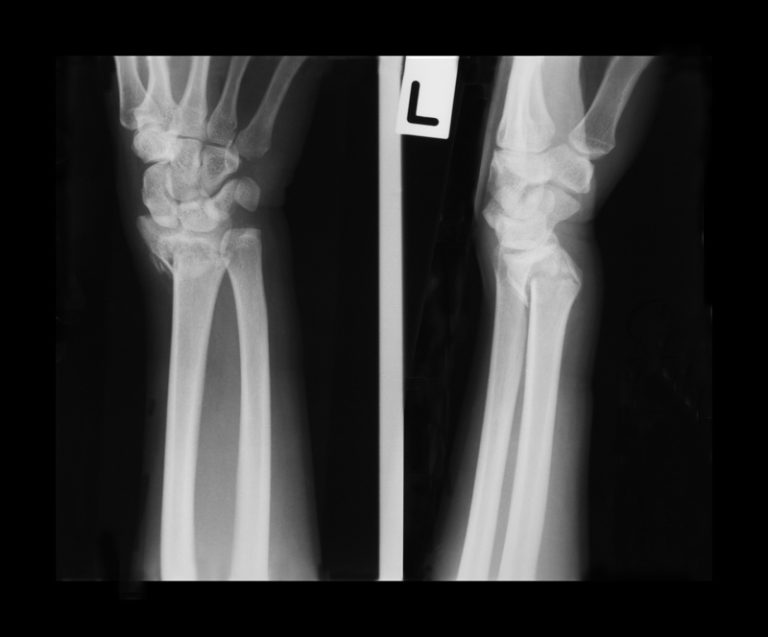

Colles' wrist fracture. Frontal Xrays of the hand and wrist bones of a Is Heat Good For Wrist Fracture restricting the movement of a broken bone in your wrist is critical to proper healing. If you have a broken wrist, you will probably need a cast, splint or sling. warmth and redness. It can happen due to an injury from a fall or when someone excessively bends or twists their wrist. The wrist consists of eight small. Is Heat Good For Wrist Fracture.